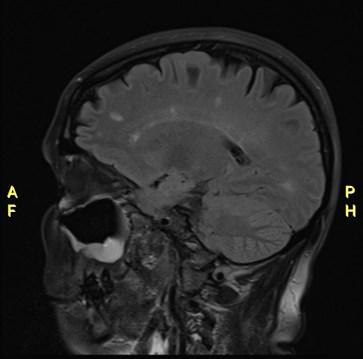

World Hypertension Day is celebrated on 17 May 2024, another important day on the health calendar. But what is hypertension and what is the buzz all about?

Blood pressure is literally the force of blood pushing against the walls of blood vessels and is measured using a blood pressure cuff. Hypertension occurs when the blood pressure through these veins is high.

What is normal blood pressure?

A normal blood pressure reading is less than 140/90 mmHg, and hypertension is defined as blood pressure more than 140/90 mmHg.

Symptoms:

Maj (Dr) Marie Schuster from 3 Military Hospital’s Family Medicine Department, says that people with very high blood pressure (180/110 or higher) can experience symptoms including headaches, chest pain, dizziness, buzzing in the ears,

World Hypertension Day

What is a hypertensive crisis?